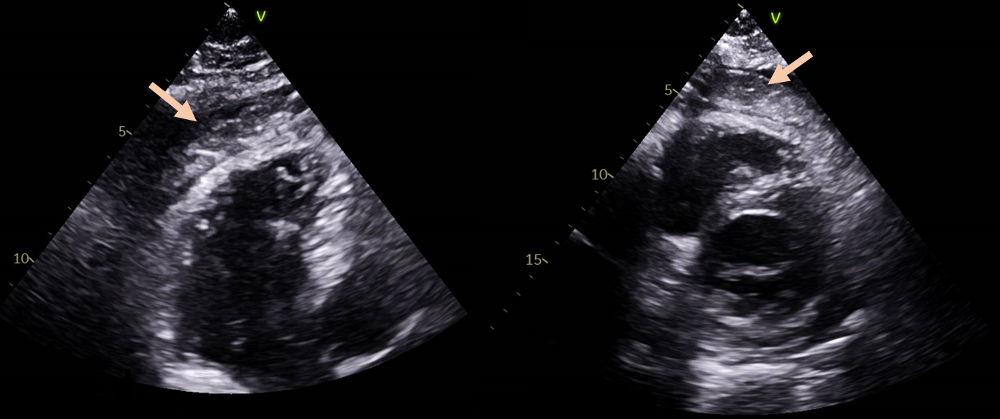

A 60-year-old male, with previous history of type 2 diabetes with mild renal insufficiency, presented to the emergency room (ER) with complaints of chest pain enhanced by respiratory motion for the past two days, with no fever or other symptoms. The electrocardiogram (ECG) showed diffuse and superiorly concave ST-segment elevation. His blood tests revealed an elevated C-reactive protein with no other significant findings and a transthoracic echocardiogram (TTE) was performed, showing a structurally normal heart, with preserved ejection fraction and a mild pericardial effusion. A diagnosis of uncomplicated pericarditis was made at this stage and the patient was discharged under colchicine 0.5 mg bid and acetylsalicylic acid 1,000 mg tid, with weaning off instructions, and a cardiology appointment was scheduled. However, the patient returned six days later, with persistency of intense chest and new onset of fever and fatigue. He was tachycardic and hypotensive. The ECG was similar to the previous one. The TTE showed a significant pericardial effusion, causing hemodynamic compromise. The patient was submitted to an emergent pericardiocentesis with hemodynamic stabilization. Blood cultures were drawn and the pericardial fluid was sent to cultural examination, revealing a leucocyte count of 152/µL. Empirical antibiotic therapy was initiated with vancomycin and ceftriaxone. Blood cultures came back negative, but a pathogenic agent was isolated in the pericardial fluid: Dermabacter hominis. As for the antimicrobial susceptibility test, there are no breakpoints to D. hominis and so the minimal inhibitory concentrations (MICs) were obtained and the breakpoints of Corynebacterium (EUCAST) were applied, given the resemblance of these agents. The same antibiotics were maintained, in accordance with the above mentioned susceptibility test. During the first 48h, the patient had a favorable evolution, however a re-elevation of C-reactive protein (CRP) occurred, along with reappearance of fever (>38°C) and chest pain. Heart computed tomography (CT) scan and transesophageal echocardiogram were unremarkable. Serial TTE assessments showed re-development of new pericardial effusion with non-pure fluid with content of heterogeneous appearance (Figure 1 [Fig. 1]). It is possible that the antibiotics used were not fully effective. Given the unfavorable evolution, the case was discussed in Heart Team and a surgical drainage with pericardiectomy was considered the best approach. The patient was submitted to a bilateral antephrenic pericardiectomy, with drainage of amorphous tissue from the pericardial sac.

Figure 1: Re-development of pericardial effusion post-pericardiocentesis

On the left: TTE image in 3 chamber view showing pericardial effusion with heterogeneous content in the pericardial space (arrow), inexistent in the TTE post pericardiocentesis; on the right: TTE image in short axis view, showing the same heterogeneous content in the pericardial space (arrow)